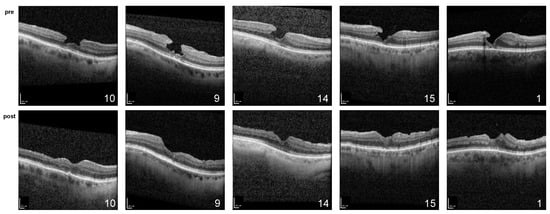

2.1. Morphological Findings

- Hagenau, F.; Luft, N.; Nobl, M.; Vogt, D.; Klaas, J.E.; Schworm, B.; Siedlecki, J.; Kreutzer, T.C.; Priglinger, S.G. Improving morphological outcome in lamellar macular hole surgery by using highly concentrated autologous platelet-rich plasma. Graefes. Arch. Clin. Exp. Ophthalmol. 2022, 260, 1517–1524. [Google Scholar] [CrossRef] [PubMed]

- Hagenau, F.; Nobl, M.; Vogt, D.; Schworm, B.; Siedlecki, J.; Kreutzer, T.; Luft, N.; Priglinger, S. Highly Concentrated Autologous Platelet-Rich Plasma Restores Foveal Anatomy in Lamellar Macular Hole Surgery. Klin. Monbl. Augenheilkd 2021, 238, 885–892. [Google Scholar] [CrossRef] [PubMed]